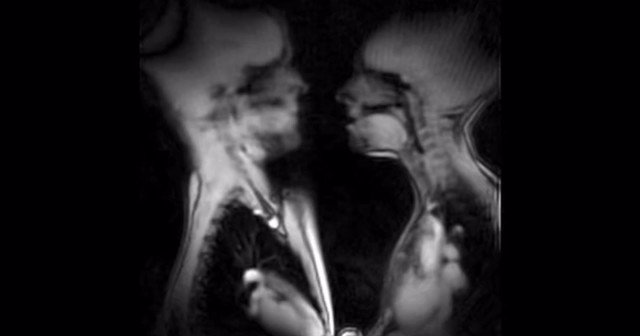

左男性、右女性、キスのMRI。心臓が強く脈打つのがわかる。内臓と内臓のコミュニケーション。

The anatomy of kissing and love In magnetic resonance imazing scanner

https://t.co/WrUH1UeWRK